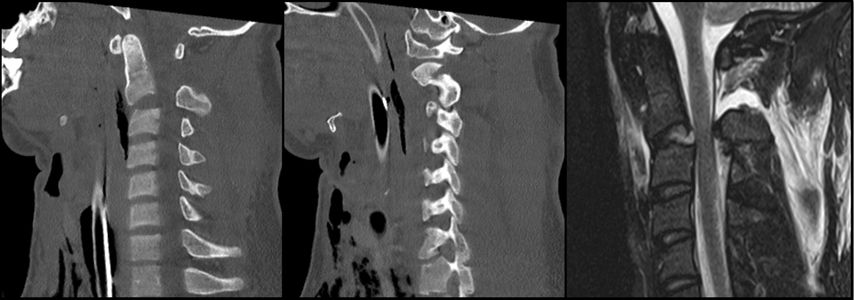

Hangman-Fraktur – traumatische Spondylolyse C2/3